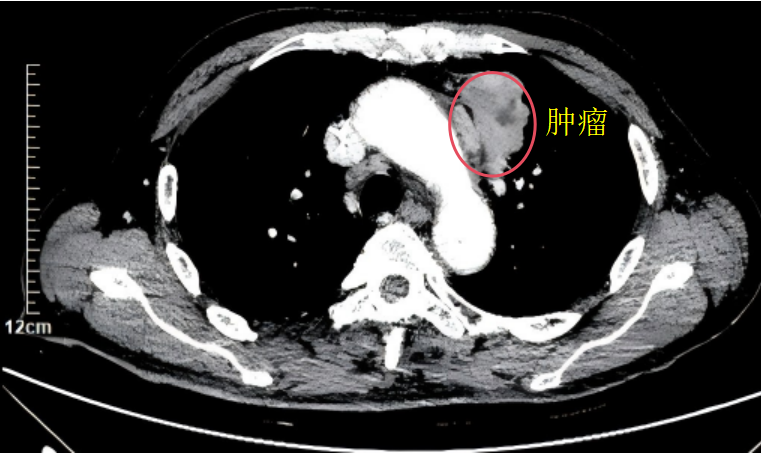

接受治疗的患者为68岁男性,此前已确诊左上肺低分化鳞癌。由于患者肺功能较差,无法耐受传统根治性手术,治疗一度陷入困境。经多学科会诊评估并取得患者及家属同意后,最终确定实施CT引导下康博刀复合式冷热消融术。

此次手术由胸外科副主任邹耀罡主任医师主刀,陈敏副主任医师与护士长杨丽华副主任护师组成的专业团队协同开展。术中,团队凭借丰富的临床经验和精准的操作技巧,在CT实时影像引导下,将直径约2mm的康博刀消融针精准置入肿瘤靶区,通过两个循环的“深度冷冻-主动复温”治疗——先将病灶温度降至-196℃的超低温,再快速升温至85℃,形成的“冰球”完整覆盖整个肿瘤病灶,实现对肿瘤组织不可逆的精准损毁。整场手术耗时短、创伤小,患者术中生命体征平稳,顺利完成,无并发症出现。术后,患者恢复良好,生活质量明显提升,一家人对治疗效果十分满意。